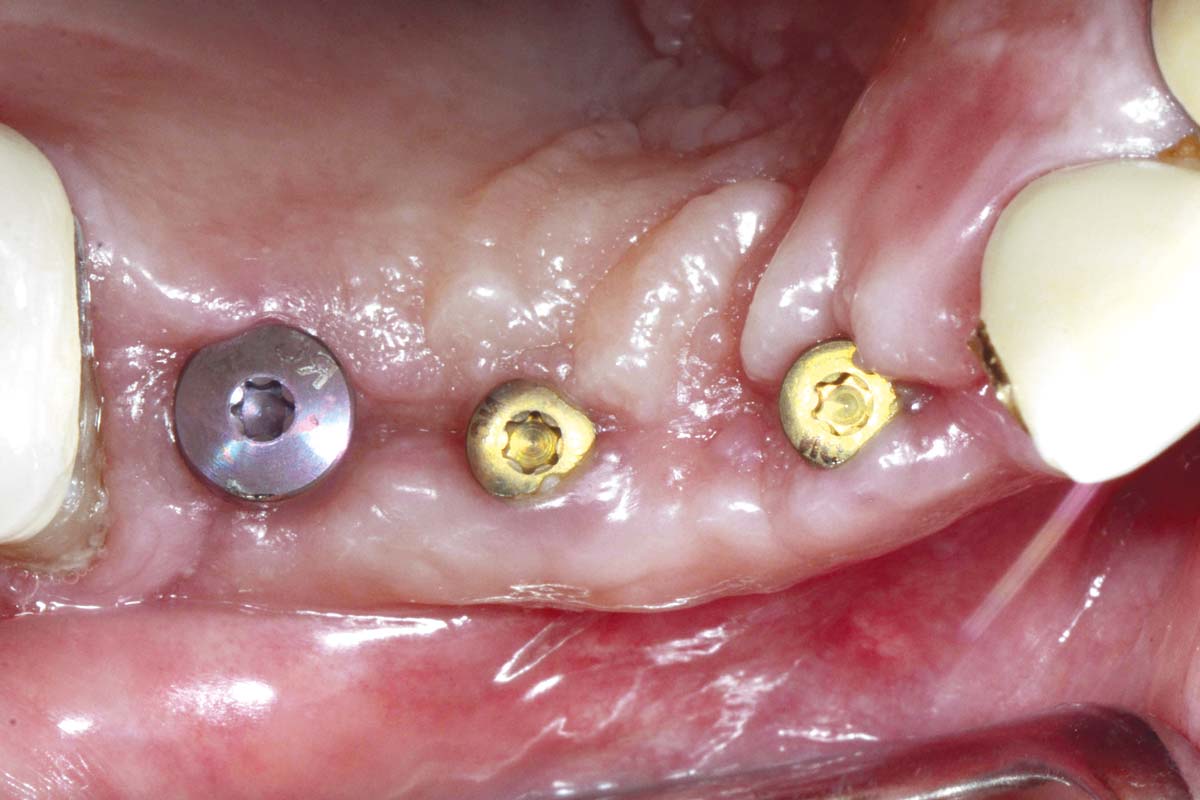

Initial clinical situation: Bone defect in the upper right maxilla (teeth #14-16)